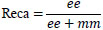

To evaluate the quality of the suggested model segmentation, we employed pixel-level metrics including accuracy, Dice coefficient, IoU, precision, recall, and F1 score. Table 3 represents the definitions of the metrics.

| S.No. | Metrics | Definition |

|---|---|---|

| 1. | Dice Score |

|

| 2. | Accuracy |

[32] [32]ee: True Positives, ff: True Negatives, nn: False Positives, mm: False Negatives |

| 3. | Precision |

|

| 4. | Recall |

|

| 5. | F1-Score |

[33] [33]

|

| 6. | IOU |

|